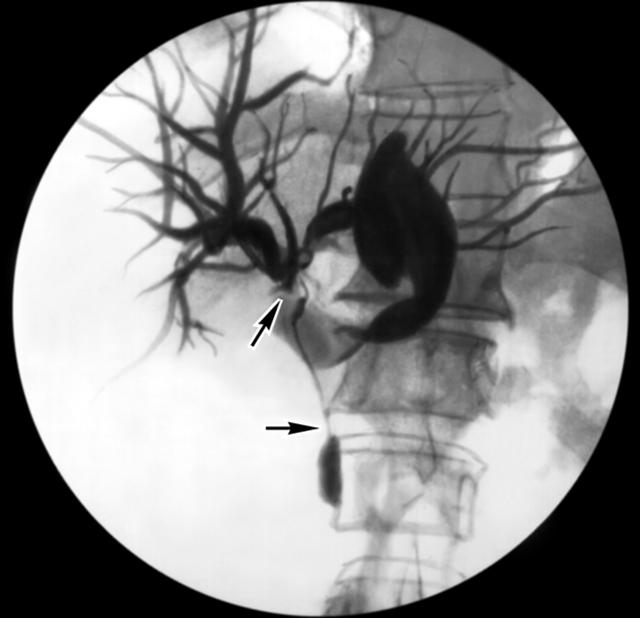

Рис. 2а). Холангиограммы больного со стриктурой общего желчного протока: выраженное сужение общего желчного протока, в области стриктуры (указана стрелками) определяется металлический проводник.